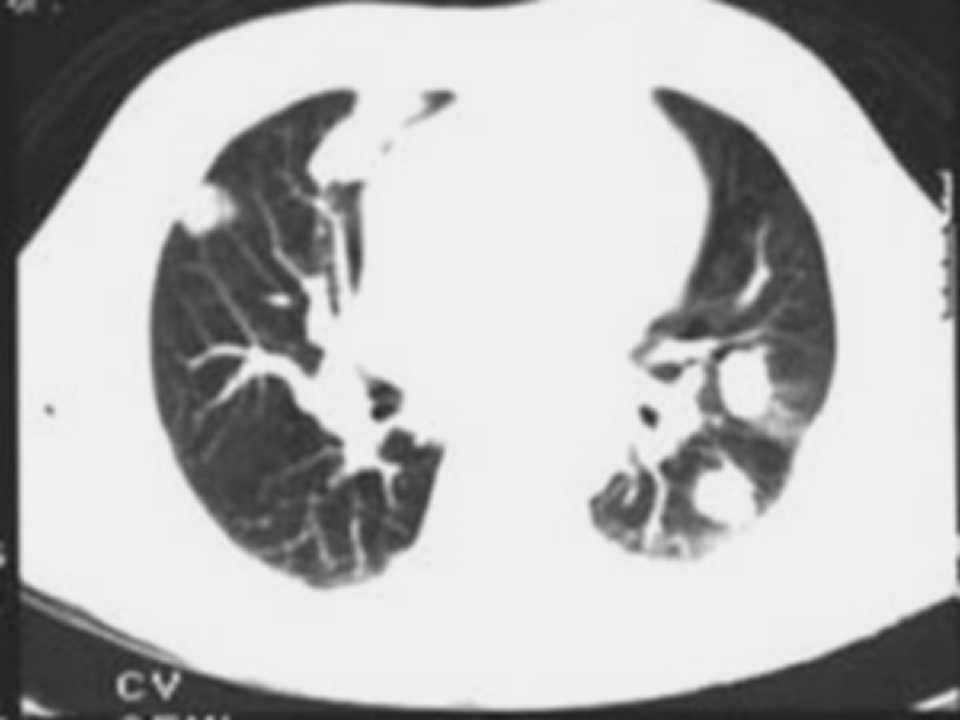

肺癌影像学表现